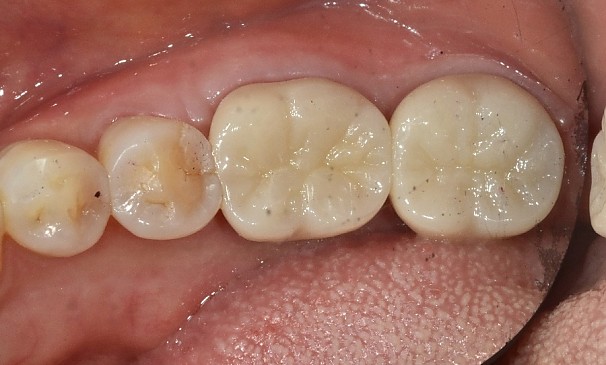

치아머리 확보술란?

선천적으로 치관(치아머리)이 짧거나, 사고로 치관의 일 부분이 깨졌을 경우,

크라운을 씌울 때 남아 있는 치관의 길이가 부족해서 크라운이 탈락할 가능성이 클 때 크라운의 길이를 확보하기 위해

잇몸 부분을 절개하여 치아 머리 부분의 길이를 확보합니다.

치아머리확보술